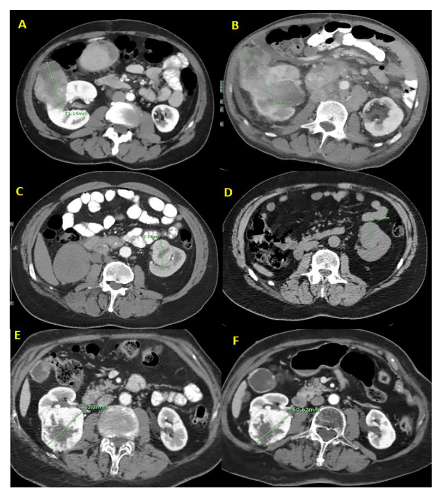

RCC diameters, time intervals, and growth rates are detailed in Table 3 and Fig. 1. Representative CT images are presented in Fig. 2. The complete set of photos and case histories is available in Supplementary Material 2. The average RCC diameter on the initial CT was 41.9 mm (SD 25.1 mm). After an average follow-up of 28.9 months (SD 29.6 months), the RCC diameter increased in 15 patients (by an average growth rate of 7.3 mm/year, SD 2.9 mm/year). In patients treated with CHOP or R-CHOP, the average growth rate was 8 mm/year (SD 3.0 mm/year). In those treated with cyclophosphamide or doxorubicin, the average growth rate was 5.9 mm/year (SD 4.5 mm/year), and in patients treated with vincristine, the average growth rate was 6.3 mm/year (SD 5.1 mm/year). The RCC diameter remained stable in four patients and decreased in two patients (by 12 mm/year in a tamoxifen-treated patient and by 3.1 mm/year in a patient treated with a combination of bevacizumab, paclitaxel, and cisplatin).

Fig. 2.

A: A 40-year-old man diagnosed with mantle cell lymphoma and Fuhrman grade 2 clear cell carcinoma. B: After 10 months and 4 cycles of R-CHOP, the tumor’s diameter increased by 10 mm.

C: A 58-year-old man diagnosed with diffuse large B-cell lymphoma and Fuhrman grade 3 clear cell carcinoma. D: After 11 months and 6 cycles of R-CHOP, the tumor’s diameter increased by 6 mm.

E: A 50-year-old woman with breast cancer and Fuhrman grade 2 clear cell carcinoma. F: After 4 months of tamoxifen, the tumor’s diameter decreased by 2.5 mm.